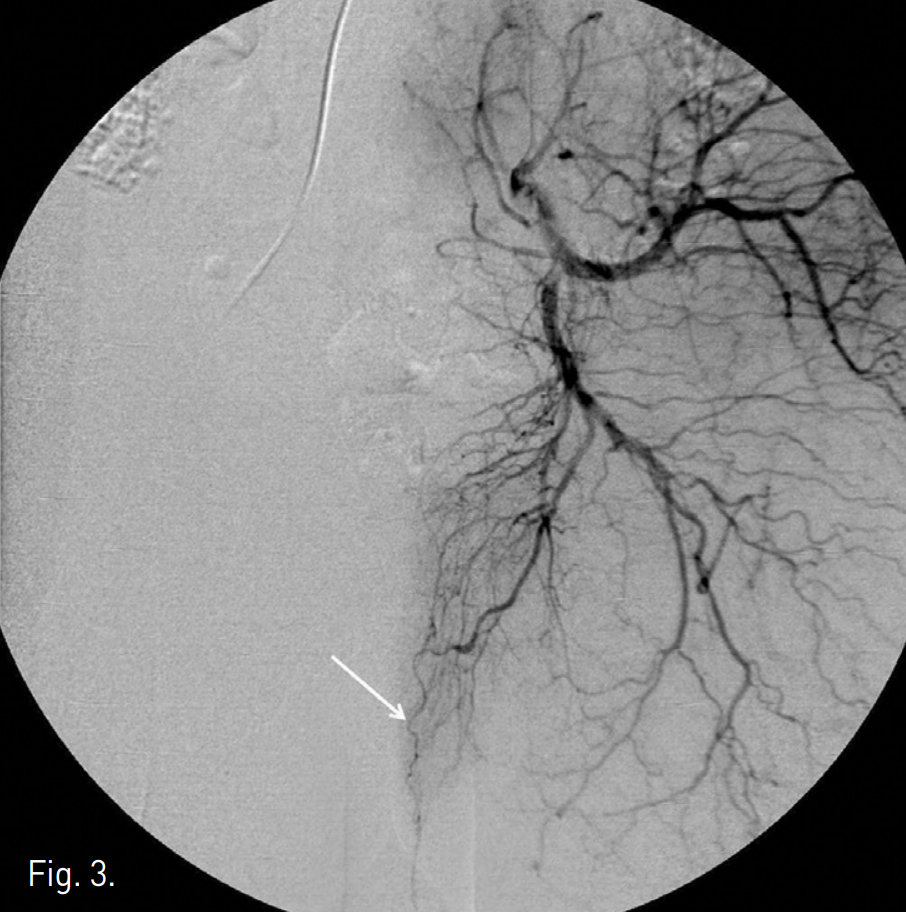

Fig. 1

Right internal iliac angiogram shows an arterio-cavernous fistula at the distal portion of a branch of the right internal pudendal artery (arrow).